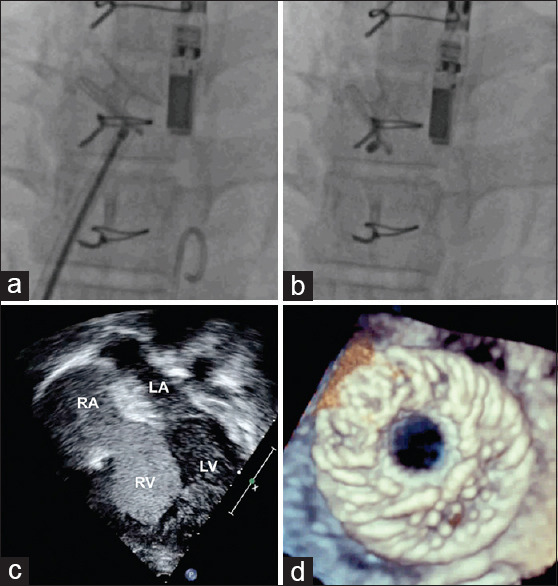

Methods: A multi-institutional study assessed the feasibility and safety of this device and reported short-term follow-up. This device, with an 8-mm fenestration diameter, was deployed after transseptal puncture using a 12F sheath.

Results: Between April 2023 and June 2024, 15 symptomatic patients aged 5-39 years, including four children, received this implant after dual pulmonary vasodilator pharmacotherapy for at least 2 years. Etiology included idiopathic PAH in eight patients, hereditary PAH in two, operated shunt lesions in four, and human immunodeficiency virus-associated PAH in one patient. The key indication was recurrent syncope in 11 and right heart failure in the rest. The mean N-terminal pro-brain natriuretic peptide was 2414 ± 2046 pg/mL. The hemodynamic assessment revealed high right atrial pressures in 80% of patients, low cardiac index in half, and suprasystemic pulmonary pressures in four patients. The procedure was completed in all patients without any complications. Pulse oximeter saturations dropped from 98% ±2% to 92% ±4%. Symptoms improved over a median follow-up of 8 months, and the device patency was confirmed in all patients except one patient who died 5 months postprocedure after a heart-lung transplantation.